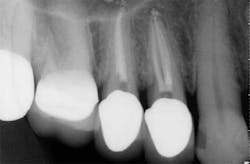

These are my least favorite teeth to treat. Most are heavily restored and the mesial-distal dimension is very small, resulting in no margin for error when locating the pulp chamber. Additionally, there can be significant inclination between the crown and root, and many will have two canals or branching at some level of the canal. (12,15) This lingual inclination of the root results in difficulty obtaining straight-line access into the buccal canal and makes locating the lingual canal almost impossible in some cases, especially if the lingual shelf of dentin is prominent. (Figure 2) Straight-line access into some lingual canals would need to be established through the mid-facial, and this is not a reasonable option for teeth restored with full-coverage crowns. (16)

have two canals. The second canal is lingual

to the main canal, and it is not uncommon for

the two canals to join at the apex. Tooth

No. 24 has a necrotic pulp and based on

the anatomy of teeth Nos. 23 and 26, a

second canal in tooth No. 24 should be expected.